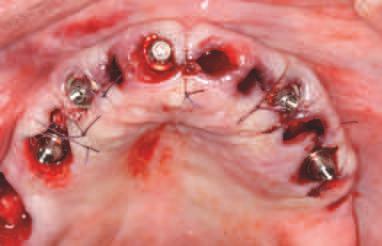

INSERAREA IMPLANTURILOR

Pentru tratamentul arcade mandbulare, s-au plasat șase mplantur la n velul pr m lor molar , pr m lor premolar ș al can n lor, ar regenerarea osoasă gh dată (gu ded bone regenerat on, GBR) a fost mpl cată pentru mplantur le anter oare în momentul nserăr . S-a obț nut

înch derea pr mară. Pac enta a cont nuat să poarte restaurarea ex stentă în t mpul v ndecăr . Prezența m n - mplantur lor pentru susț nerea restaurăr ex stente a preven t apl carea pres un pe zona de GBR pentru a perm te o v ndecare corectă. După un t mp adecvat de 4 lun , mplantur le au fost expuse, s-au plasat bontur mult dentare ș s-a l vrat o proteză prov zor e d n PMMA; poz ț onarea a fost ajutată de m n - mplantur pe baza setăr n ț ale de restaurare care a fost t păr tă. După preluarea c l ndr lor temporar , m n - mplan-

11. La mandibulă, implanturile au fost plasate fără a interfera cu mini-implanturile existente.

în t mpul etapelor de tratament până la convers a setăr prov zor în proteza ntermed ară med ată înșurubată, deoarece poz ț a lor nu a nterferat cu locaț a ș d str buț a no lor mplantur mand bulare. Însă în cazul arcade max lare, m n - mplantur le trebu au să f e îndepărtate îna nte de nserarea no lor mplantur (f g. 8-10).

La arcada max lară, procedura a debutat cu îndepărtarea m n - mplantur lor ex stente, f nd pos b lă afrontarea țesutur lor mo . S-a utl zat un gh d ch rurg cal suportat de țesut moale pentru or entarea freze p lot, ar mplantur le posteroare angulate au fost alese pentru a ev ta s nusur le pneumat zate. S-au nserat șase mplantur cu o d strbuț e antero-poster oară adecvată, obț nându-se o bună stab l tate pr mară. Restaurarea prov zor e med ată a fost convert tă într-o restaurare f xă prov zor e suportată de mplantur pe baza setăr restaurator n ț ale.